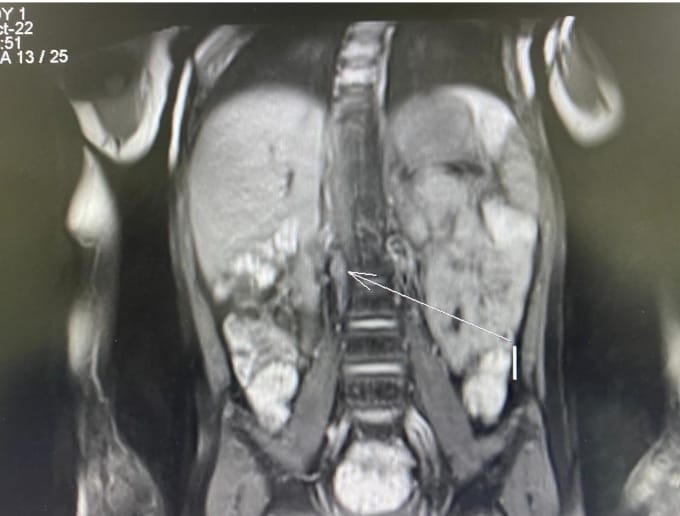

Нейробластома - это эмбриональная опухоль симпатической нервной системы, которая характеризуется агрессивным неуправляемым ростом и бурным метастазированием. Не смотря на разработанные схемы терапии прогноз для больных группы высокого риска остаётся неблагоприятным. Одним из достижений в лечении нейробластомы группы высокого риска является иммунотерапия с применением динутуксимаба бета (Карзиба), который позволяет повысить шансы на выздоровление данным пациентам. Однако применение Карзибы до недавнего времени не представлялось возможным ввиду его высокой стоимости и отсутствия регистрации.